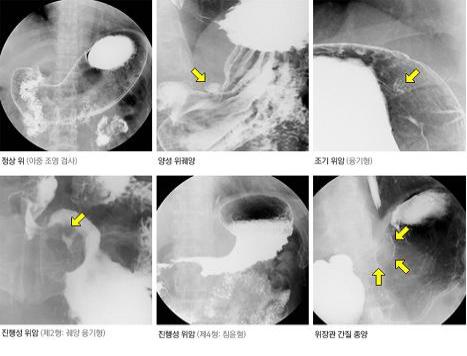

위암의 선별검사로 사용될 수 있는 방법이나 위암 진단에 있어 직접 관찰하는 위 내시경 검사에 비해 진단율이 낮고 조직검사가 불가능하여 상부위장관 조영술로 이상소견이 발견되거나 소견이 불분명한 경우에는 위 내시경 검사를 통해 재검사를 해야 한다. 방사선을 이용하는 검사이므로 임산부는 불가능하며 청력 저하, 거동이 불편하거나, 검사에 협조가 어려운 환자에게는 상부 위장관 조영술이 어려울 수 있다.

종류 위가 팽창되지 않은 상태에서 조영제를 위에 채우고 검사하는 단일 조영검사와, 발포제를 먹고 위를 팽창시킨 상태에서 위벽에 조영제를 코팅하여 위벽의 병변 유무를 검사하는 이중 조영